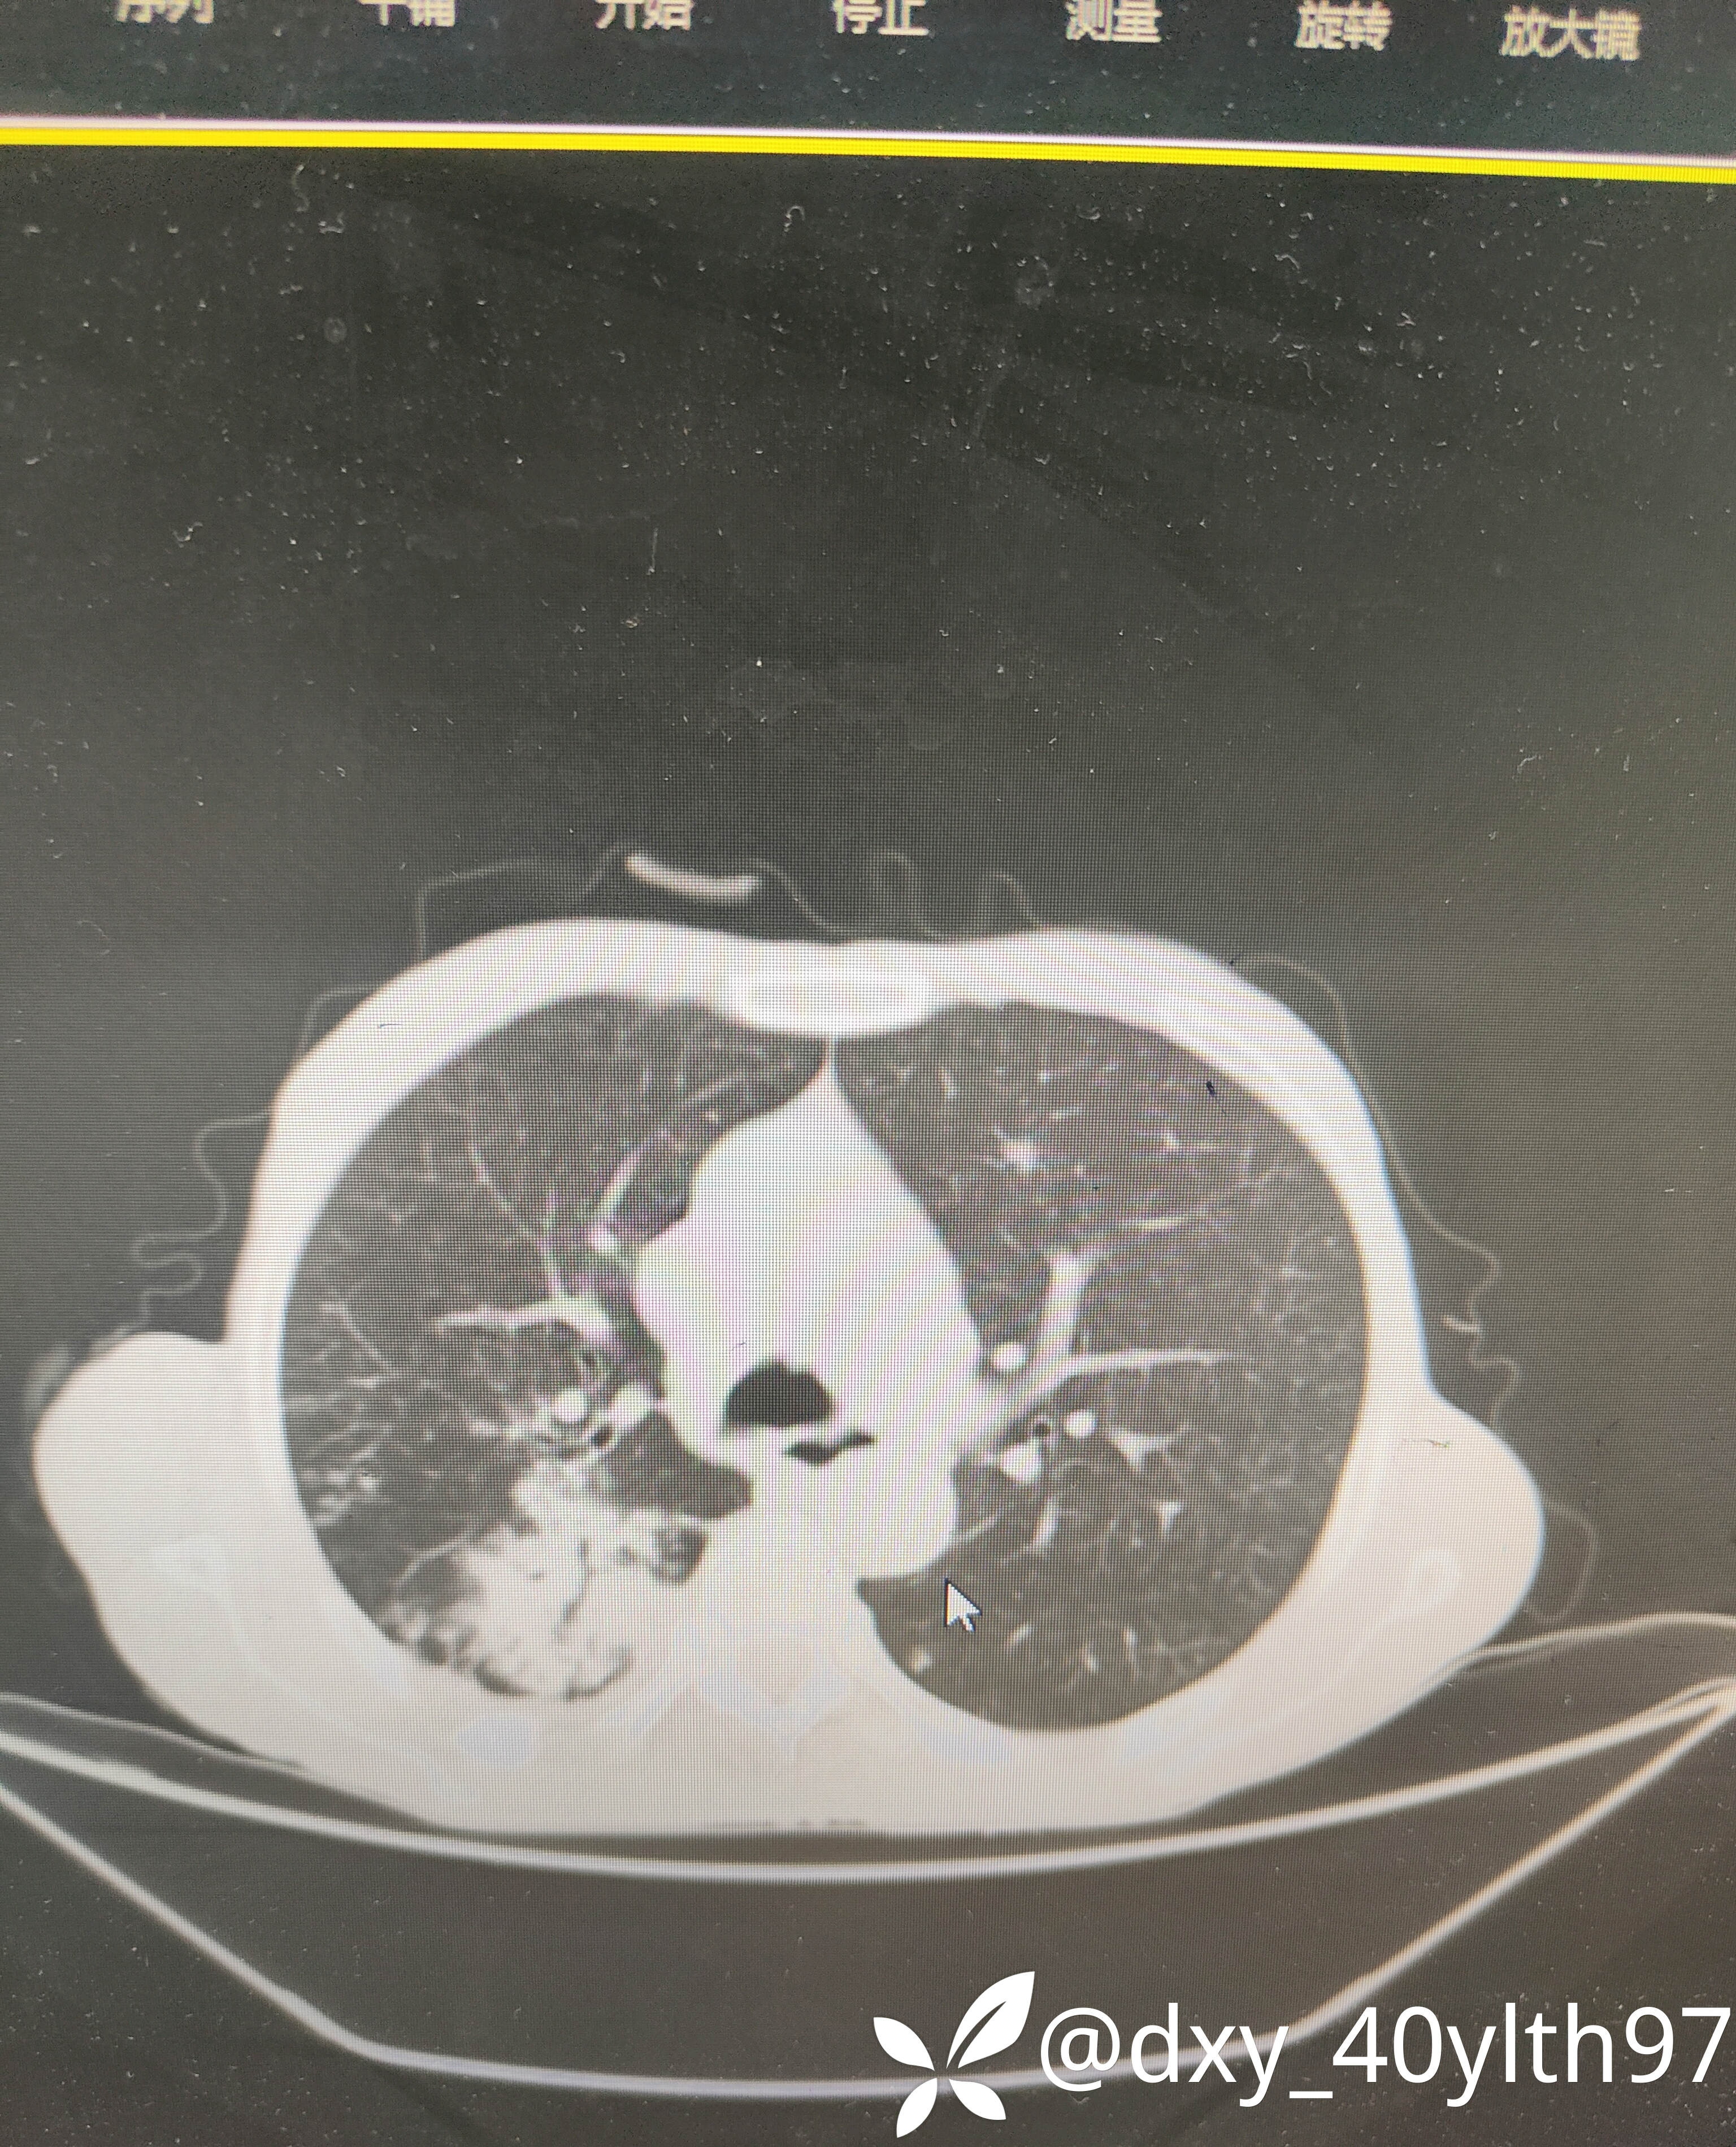

2023年8月肺部CT平扫影像结果提示:1.右肺上叶密度增高影较前显著增大,建议进一步检查;2.两肺多发斑片结节灶较前增多,部分增大。

肺部增强CT影像学提示:右肺内大片不规则影轻度强化,肿瘤可能。